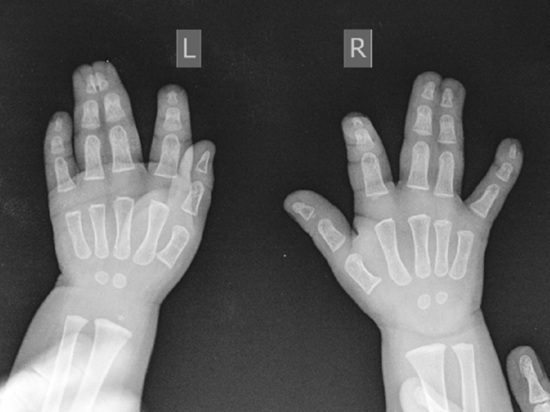

В НМИЦ ТО имени академика Г. А. Илизарова Минздрава России полуторагодовалому малышу из Тюменской области исправили врожденную аномалию развития кисти, разделив сросшиеся пальчики. Данная аномалия у него на обеих руках.

В Центре Илизарова сообщили, что у ребенка была полная кожная синдактилия III – IV пальцев правой кисти, кожно-костная синдактилия III – IV пальцев левой кисти. Пациентов с такой патологией лечат по методике, разработанной врачами Центра на основе открытия Илизарова и его аппарата.

На данный момент разделили сросшиеся пальчики на одной руке. Далее пройдет такая же операция на другой руке. Специалисты уверены, что у ребенка будут кисти, которыми он сможет полноценно пользоваться в жизни.